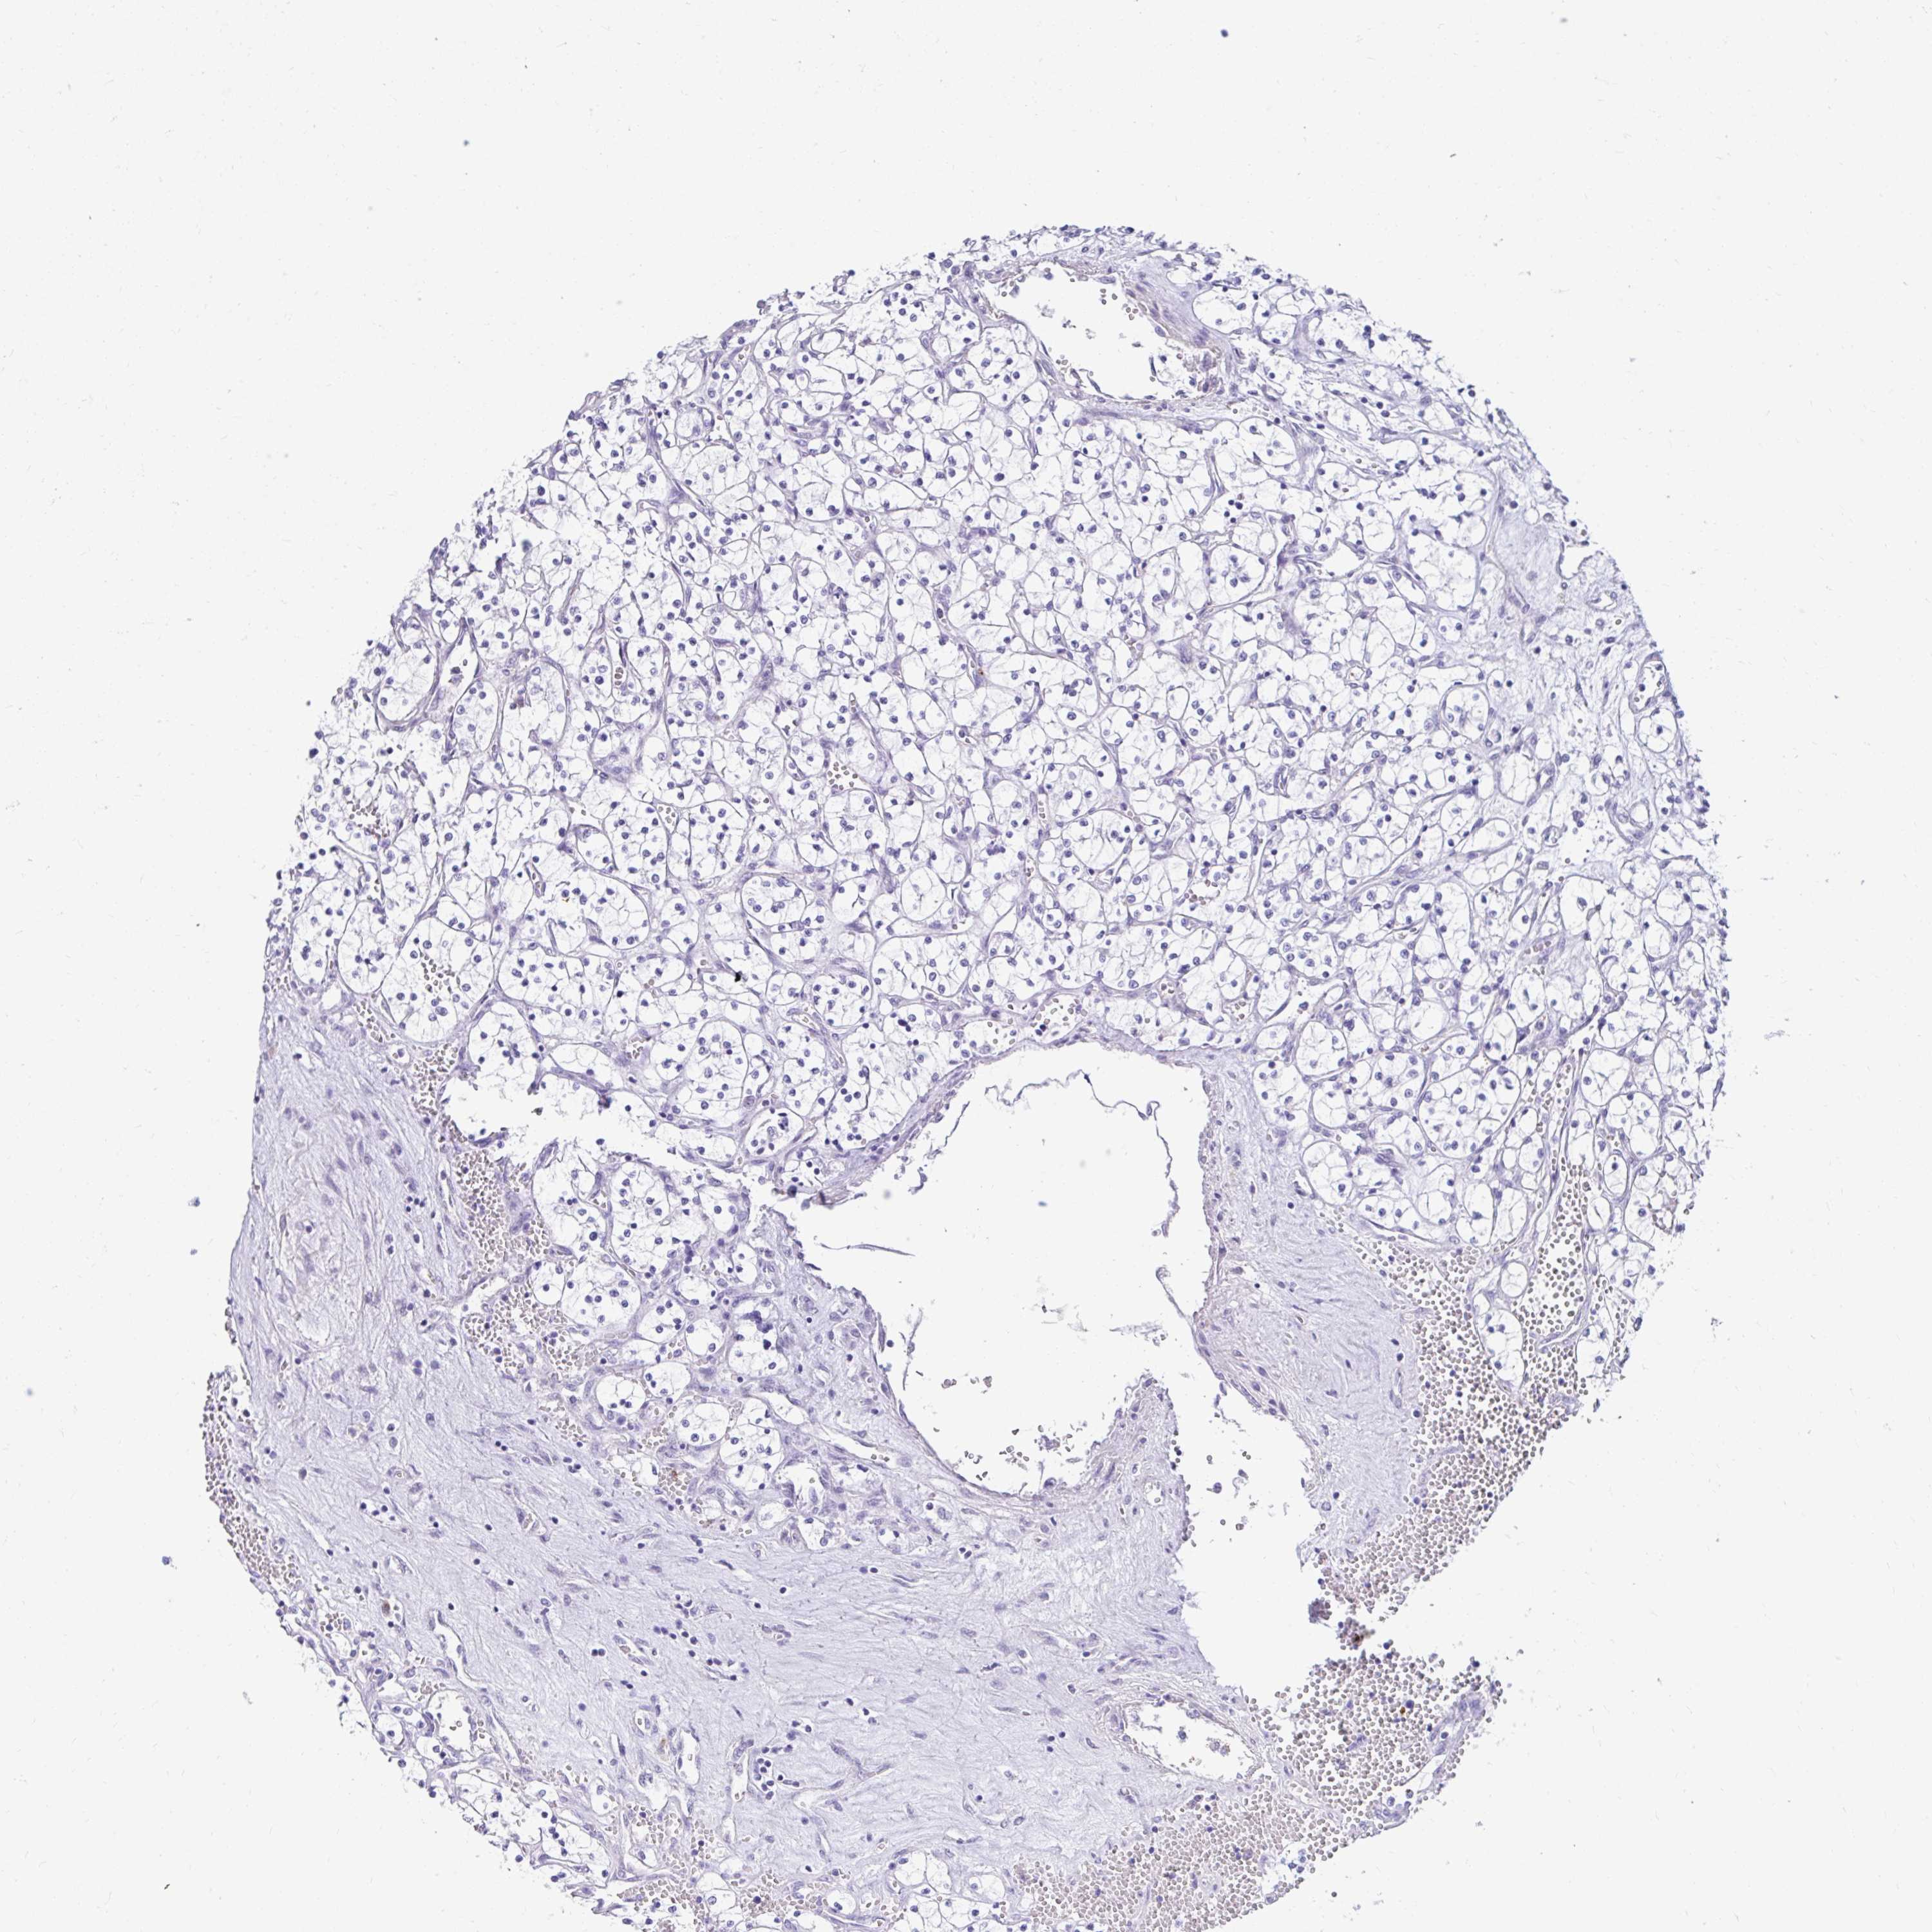

KIDNEY RENAL CLEAR CELL CARCINOMA (VALIDATION) - Interactive survival scatter ploti

The Survival Scatter plot shows the clinical status (i.e. dead or alive) for all individuals in the patient cohort, based on the same data that underlies the corresponding Kaplan-Meier plots. Patients that are alive at last time for follow-up are shown in blue and patients who have died during the study are shown in red.

The x-axis shows the expression levels (FPKM) of the investigated gene in the tumor tissue at the time of diagnosis. The y-axis shows the follow-up time after diagnosis (years). Both axes are complimented with kernel density curves demonstrating the data density over the axes. The top density plot shows the expression levels (FPKM) distribution among dead (red) and alive patients (blue). The right density plot shows the data density of the survived years of dead patients with high and low expression levels respectively, stratified using the cutoff indicated by the vertical dashed line through the Survival Scatter plot. This cutoff is automatically defined based on the FPKM cutoff that minimizes the p-score. The cutoff can be changed by dragging the vertical line or by entering a cutoff value in the square labeled "Current cut-off".

Under the Survival Scatter plot the p-score landscape (black curve; left axis) is shown together with dead median separation (red curve; right axis). Dead median separation is the difference in median mRNA expression between patients who have died with high and low expression, respectively. It is calculated as follows: median FPKM expression of dead patients with high expression - median FPKM expression of dead patients with low expression. This is intended to aid the user in visually exploring custom cutoffs and the associated p-scores and dead median separation.

Individual patient data is displayed and can be filtered by clicking on one or more of the category buttons on the top of the page. Categories describing expression level and patient information include: high, low, alive, dead, female, male and tumor stages. The scale of the x-axis can be toggled between linear and log-scale by clicking on the "x log" button. Mouse-over function shows TCGA ID, patient information and mRNA expression (FPKM) for each patient.

& Survival analysisi

Kaplan-Meier plots summarize results from analysis of correlation between mRNA expression level and patient survival. Patients were divided based on level of expression into one of the two groups "low" (under cut off) or "high" (over cut off). X-axis shows time for survival (years) and y-axis shows the probability of survival, where 1.0 corresponds to 100 percent.

DCAF17 is not prognostic in Kidney Renal Clear Cell Carcinoma (validation)

Best expression cut offi

Based on the FPKM value of each gene, patients were classified into two groups and association between prognosis (survival) and gene expression (FPKM) was examined. The best expression cut-off refers the FPKM value that yields maximal difference with regard to survival between the two groups at the lowest log-rank P-value. Best expression cut-off was selected based on survival analysis .

When clicking on this number, the vertical dashed line indicating cut-off, the interactive survival plot, and the Kaplan-Meier curve will be adjusted to show results based on the best expression cut-off.

: 5.98

P scorei

Log-rank P value for Kaplan-Meier plot showing results from analysis of correlation between mRNA expression level and patient survival.

N/A

TCGA RNA samplesi

RNA-seq data is reported as average FPKM (number Fragments Per Kilobase of exon per Million reads), generated by the The Cancer Genome Atlas (TCGA) .

Normal distribution across the dataset is visualized with box plots, shown as median and 25th and 75th percentiles. Points are displayed as outliers if they are above or below 1.5 times the interquartile range. FPKM values of the individual samples are presented next to the box plot.

Average pTPM 6.5

Number of samples 100